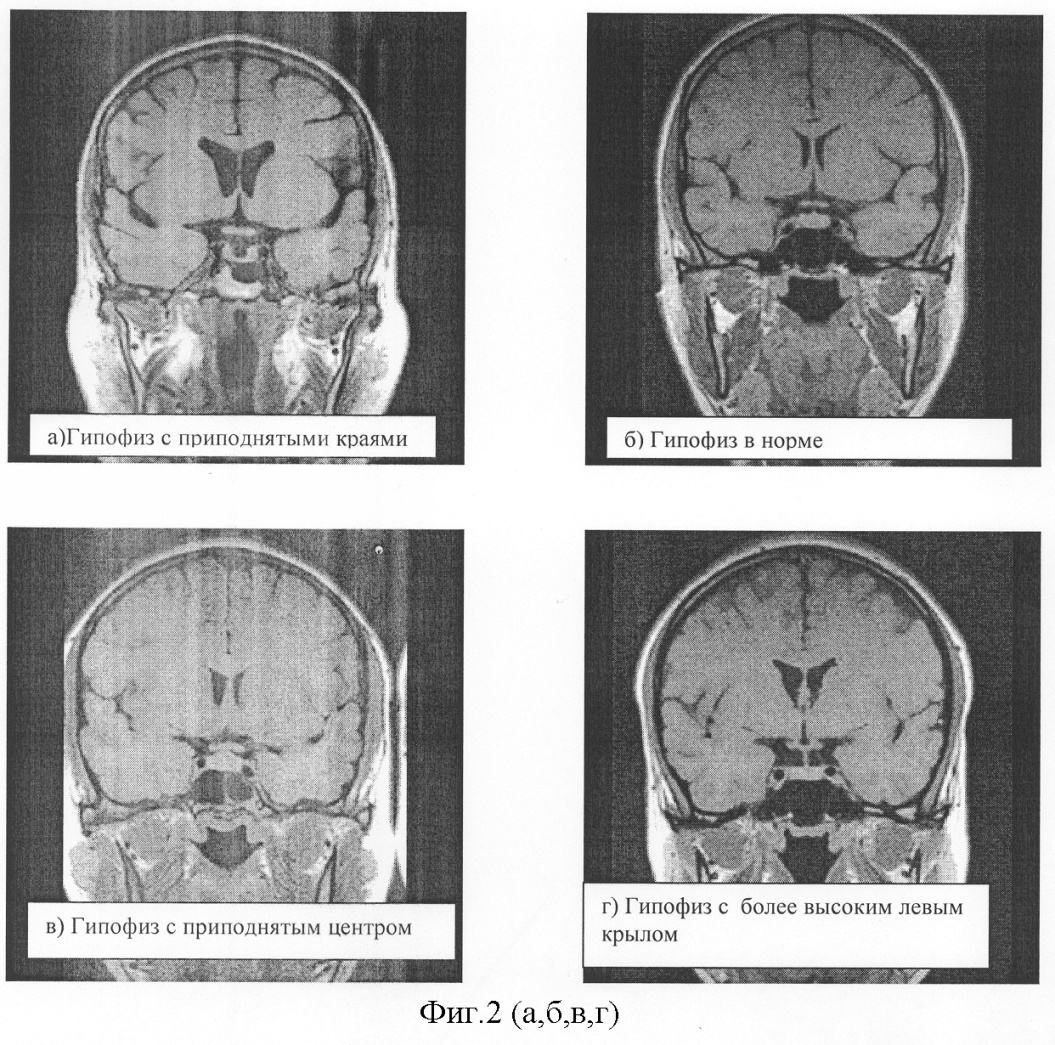

Особенно часто такая ошибка расчета возникает в случаях широкого или узкого турецкого седла и измененных формах гипофиза (фиг.1). Такая ошибка возникает при косом расположении гипофиза, приподнятом одном или обоих краях, возвышающемся левом или правом крыле гипофиза или их разнонаправленности, а также в случаях аденом гипофиза, имеющих разнонаправленный фестончатый рост. В этих ситуациях объем гипофиза, рассчитанный по формуле V=1/2·H·W·L, будет сильно определяться местом измерения параметров высоты, ширины или длины. Существуют варианты гипофиза, когда латеральный размер вообще трудно выделить (фиг.2).

Ниже схематически представлены наиболее часто встречаемые формы гипофизов по фронтальным сечениям (фиг.1), при расчете объема которых по формуле Di-Chiro Nelson возникает ошибка измерения, иногда достигающая 30 и даже 50%. Разнообразие форм гипофиза, как правило, определяется формой турецкого седла, варианты строения которого зависят от формирования и развития костей черепа. Далее приведены в качестве иллюстраций томограммы гипофизов во фронтальных сечениях (фиг.2).

На фиг.2 представлены магнитно-резонансные томограммы вариантов гипофиза, полученные во фронтальных сечениях. При этом на фиг.2а показан гипофиз в узком турецком седле; 2б – круглый гипофиз в косом турецком седле; 2в – корытообразный гипофиз в косом турецком седле; 2г – гипофиз с уменьшенным правым крылом; 2д – гипофиз с заостренными краями; 2е – гипофиз с закругленными краями; 2и – гипофиз в узком турецком седле; 2ж – гипофиз в косом седле; 2з – корытообразный гипофиз в косом седле; 2к – гипофиз с уменьшенным правым крылом; 2л – гипофиз с приподнятыми крыльями; 2м – гипофиз в пустом турецком седле.